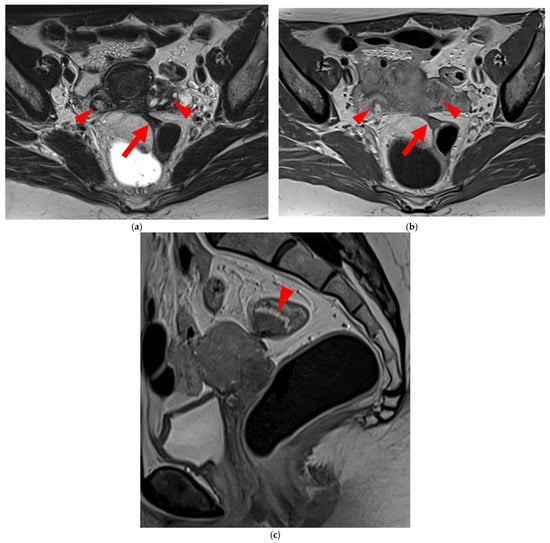

Figure 15. Pelvic MRI scan of a patient with a “kissing ovaries” sign and rectal involvement (i.e., HTD type 6 USLs). (a,b) Axial T2WI (a) and contrast-enhanced T1WI (b) show both ovaries in close proximity (“kissing ovaries” sign) (arrowheads) and rectosigmoid wall infiltration (arrows). (c) Sagittal contrast-enhanced T1WI shows rectosigmoid wall infiltration, appearing as a “medallion-shaped” lesion outlined by markedly enhancing mucosa (arrowhead).

2.3.1. “Kissing Ovaries”: A Form Straddling Between Type 5B and Type 6 USLs

Besides endometriomas, another type of ovarian involvement in DIE includes adhesions that cause the ovaries to retract medially across the midline, behind the uterus, into the pouch of Douglas. When the ovaries are displaced medially and are in close proximity, they are commonly referred to as “kissing ovaries”. Additionally, medialized ovaries on preoperative imaging expose the digestive tract to a 20% risk of involvement [22]. In our experience, the injection of a contrast agent is useful when there is doubt about an endometriotic rectosigmoid invasive lesion on T2WI, especially if a rectal filling was not performed. A markedly enhancing mucosa, which outlines rectosigmoid local wall thickening on post-contrast T1WI without fat suppression (forming a “medallion-shaped” lesion), is a valuable aid to diagnosis.

In the HTD MRI classification of USLs, the “kissing ovaries” sign is considered a form between types 5B and 6. In the case of concomitant rectal involvement, the USL is classified as type 6 (Figure 15); otherwise, it is classified as type 5B (comparable to a nodule with spiculated margins).